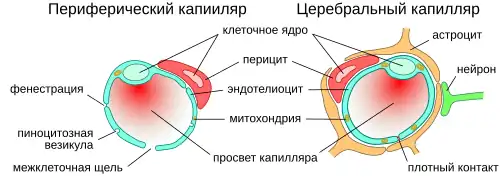

Основным элементом структуры ГЭБ являются эндотелиальные клетки. Особенностью церебральных сосудов является наличие плотных контактов между эндотелиальными клетками. В структуру ГЭБ также входят перици́ты и астроци́ты[23]. Межклеточные промежутки между эндотелиальными клетками, перицитами и астроцитами — нейроглии , меньше, чем промежутки между клетками в других тканях организма. Эти три вида клеток являются структурной основой ГЭБ не только у человека, но и у большинства позвоночных[28][29].

Эндотелий

Капиллярные сосуды выстланы эндотелиальными клетками. Эндотелий сосудов большинства тканей содержит открытые промежутки (фенестра́ции) диаметром около 50 нм и межклеточные щели от 100 до 1000 нм. Через эти промежутки вода и растворённые в ней вещества циркулируют между кровью и межклеточным пространством. Отличительной особенностью сосудов центральной нервной системы является отсутствие как фенестраций, так и межклеточных щелей между эндотелиальными клетками[30]. Таким образом, эндотелиальная выстилка капилляров мозга является сплошной[31].

Другим отличием эндотелия церебральных капилляров от периферических является низкое содержание в них пиноцито́зных пузырьков (вези́кул)[9][32].

Количество митохондрий в эндотелиальных клетках сосудов мозга в 5-10 раз выше, чем в эндотелии периферических сосудов. Столь высокое содержание митохондрий связано со значительными энергетическими потребностями эндотелиальных клеток ГЭБ, осуществляющих активный транспорт и обмен веществ[27]. (Митохондрии — это органеллы, в которых происходит синтез молекул АТФ, являющихся основным источником энергии для клеток.)

Астроциты

Астроциты — большие нейроглиальные клетки звёздчатой формы. Своими отростками они выстилают стенки мозговых капилляров со стороны мозговой ткани. В то же время, несмотря на то, что пластинчатыми окончаниями их клеточных отростков выстлано около 99 % капиллярных сосудов, астроциты не выполняют прямой барьерной функции[29][74]. Астроциты тесно взаимодействуют с эндотелиальными клетками. Между ними осуществляется постоянный обмен веществ[75]. Астроглиальные клетки индуцируют возникновение и формирование ГЭБ. При проведении экспериментов по пересадке сосудов мозга в периферические органы и наоборот — периферических сосудов в ткань головного мозга, отмечено формирование ГЭБ в периферических сосудах, пересаженных в мозг (образование плотных контактов, перестройка эндотелиальных клеток), и разобщение эндотелиальных клеток и появление фенестраций между ними при пересадке мозговых сосудов[23][76]. Также in vitro показано влияние астроцитов на фенотип эндотелия. В клеточной культуре, содержащей астроциты и эндотелиоциты, отмечено более плотное расположение эндотелия по сравнению с его чистой клеточной культурой[77].